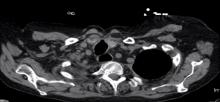

Featured Image:

Tracheocutaneous fistulas are infrequent complications of prolonged tracheostomies. This video explains the technique used at the authors’ institution for closure of a tracheocutaneous fistula in the context of a clinical case. The critical steps are: